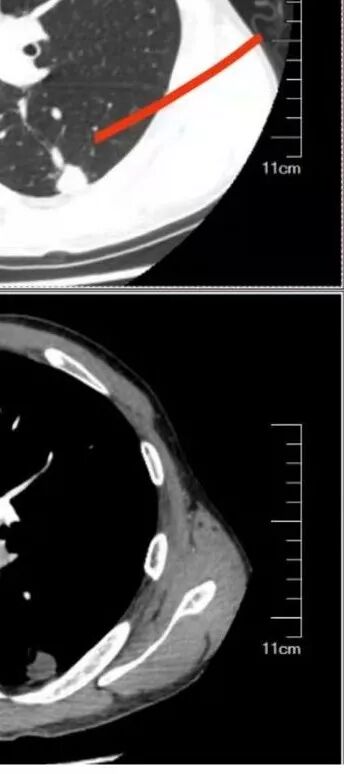

岁月:

我会做一做支气管的CPR,肺动脉的CPR。

因为南边的考虑一定要看到支气管,怎么办呢?

我很早以前做早癌,就是用CPR技术来观看病灶与支气管、血管的关系。

wonderful:

薄层

我的重建图像大部分是这样。

360旋转,可以观看意想不到的效果,我一直很重视这两种重建方法。比想象好 直观。